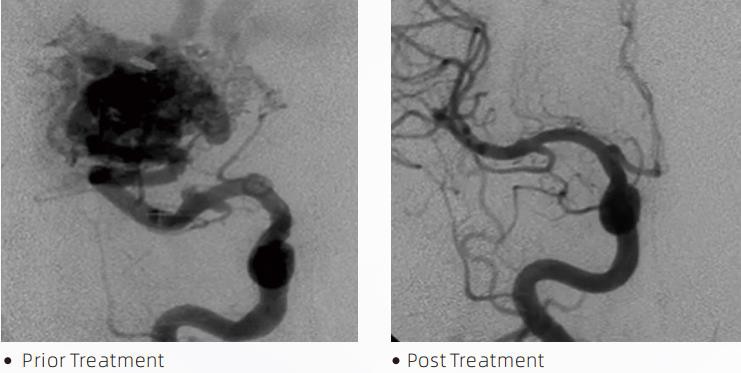

Y LafaTMMae System Embolig Hylif yn therapi endofasgwlaidd ymyriadol ar gyfer trin camffurfiadau serebro-fasgwlaidd. Mae camffurfiad serebro-fasgwlaidd yn cyfeirio at grŵp o annormaleddau niwrofasgwlaidd anfalaen neu falaen a all arwain at hemorrhage mewngreuanol, cnawdnychiant yr ymennydd, isgemia cerebral a chlefydau eraill. Mae'r system embolization hylif yn ddyfais feddygol a weinyddir trwy fewnosod mewnfasgwlaidd syml, sy'n embolizes pibellau gwaed cerebral annormal trwy chwistrellu deunydd hylif arbennig. Mae'r defnydd hylif yn ffurfio emboledd meinwe rheoledig o fewn pibellau gwaed, a all leihau effaith camffurfiadau serebro-fasgwlaidd ar gleifion. Defnyddir micro-gathetr danfon sy'n gydnaws â DMSO a nodir i'w ddefnyddio yn y niwrofasgwlaidd i gael mynediad i'r safle emboleiddio. Mae asiant embolig hylif lafa yn system asiant embolig hylif nad yw'n gludiog sy'n cynnwys copolymer EVOH (alcohol finyl ethylene) wedi'i hydoddi mewn DMSO (dimethyl sulfoxide), a phowdr tantalwm micronedig wedi'i atal i ddarparu cyferbyniad ar gyfer delweddu o dan fflworosgopi. LafaTMar gael mewn tri ffurfiant cynnyrch, LAVA-12, LAVA-18 a LAVA-34. LAVA-12: Argymhellir wrth fwydo microlestri distal a thrwy borthwyr bach. LAVA-18: Argymhellir pan fydd pigiadau pedicle bwydo yn cael eu cynnal yn agos at y nidus; LAVA-34: Argymhellir ar gyfer emboleiddio llif uwch a chydrannau dwrn mwy.